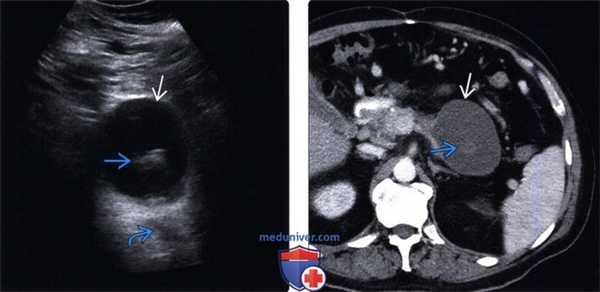

(Правый) Трансабдоминальное УЗИ, поперечное сканирование: визуализируется расширение панкреатического протока и два вытянутых скопления жидкости с четким контуром и внутренними эхосигнала-ми, располагающиеся в области шейки и тела поджелудочной железы, что характерно для сложной псевдокисты вследствие тяжелого панкреатита. (Левый) Трансабдоминальное УЗИ, поперечное сканирование: гиперэхогенное солидное образование в области головки поджелудочной железы, с умеренным кистозным компонентом, и с более эхогенным центром.

(Правый) Аксиальная КТ с контрастированием: лучше визуализируются множественный мелкие кисты внутри образования, разделенные тонкими перегородками, соединяющимися в центре.